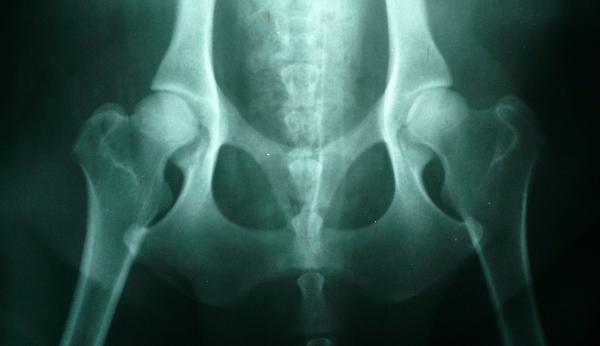

- Artrosis de cadera o coxofemoral. Es una articulación fundamental para el cuerpo, así que cualquier clase de traumatismo va a afectar la calidad de vida de las personas. En este caso se trata de modificaciones en el cartílago articular. Es una enfermedad degenerativa que implicará una inmovilización de toda el área.

- Osteogénesis imperfecta. Es una enfermedad que casi siempre se la menciona como enfermedad de los huesos de cristal. En este caso son todos los tejidos óseos los que están involucrados. Se da como resultado de un problema congénito o en su defecto como una herencia a nivel genético que se repite entre varios miembros de la familia.

- Necrosis de cadera. Es una referencia a un tipo de muerte del tejido en toda la zona o a un proceso bastante similar al descrito. Es una situación que inicia con una irrigación de sangre insuficiente. Además hay pocas posibilidades de corrección e identificación, por lo que paulatinamente se hará crónico.